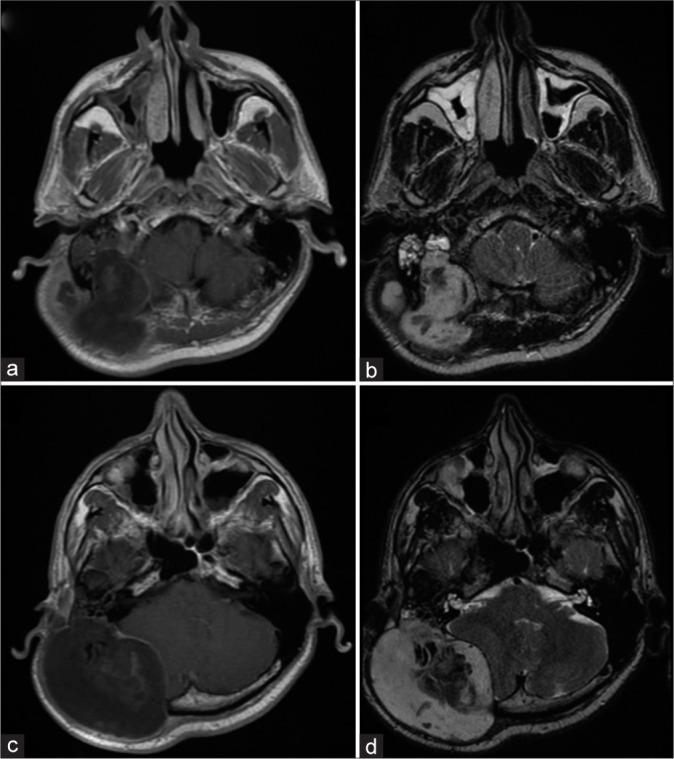

A 46-year-old reported right-sided hearing loss and a painful right retroauricular mass for 4 months. Magnetic resonance imaging revealed a 8.7 × 7.6 × 6.4 cm mass invading the right temporal and occipital bones. After a biopsy and 3 surgical procedures over 6 months, the diagnosis of TBSCC was obtained. Due to invasion of the cerebellar tissue and obstructive hydrocephalus, a ventriculoperitoneal shunt was performed. The patient was referred for adjuvant radiotherapy. However, palliative care was initiated due to tumor progression.

一名46岁患者报告右侧听力丧失和右侧耳后疼痛性肿块4个月。磁共振成像显示一个8.7×7.6×6.4 cm的肿块侵犯右侧颞骨和枕骨。经过活检和6个月内的3次手术,确诊为TBSCC。由于小脑组织受侵犯和梗阻性脑积水,进行了脑室腹腔分流术。患者被转诊接受辅助放疗。然而,由于肿瘤进展,开始了姑息治疗。